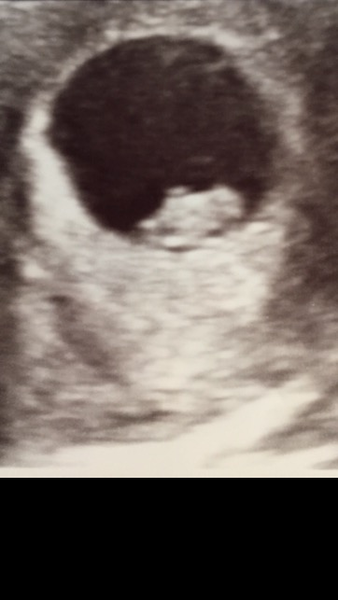

The scan went really well! Was so reassuring to see the little flickering heartbeat and that it's all where it's supposed to be!

The lady was really good, pointing out the areas that would develop into arms and legs and the head. Definitely feels more real and has helped me relax about not feeling too sick!